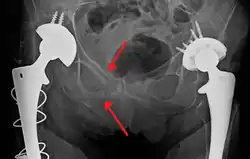

Blunt pelvic trauma

The most common causes of blunt pelvic trauma are motor vehicle accidents and multiple-story falls, and thus pelvic injuries are commonly associated with additional traumatic injuries in other locations.[28] In the pelvis specifically, the structures at risk include the pelvic bones, the proximal femur, major blood vessels such as the iliac arteries, the urinary tract, reproductive organs, and the rectum.[29][28]

.png)

One of the primary concerns is the risk of pelvic fracture, which itself is associated with a myriad of complications including bleeding, damage to the urethra and bladder, and nerve damage.[30] If pelvic trauma is suspected, emergency medical services personnel may place a pelvic binder on patients to stabilize the patient's pelvis and prevent further damage to these structures while patients are transported to a hospital. During the evaluation of trauma patients in an emergency department, the stability of the pelvis is typically assessed by the healthcare provider to determine whether fracture may have occurred. Providers may then decide to order imaging such as an X-ray or CT scan to detect fractures; however, if there is concern for life-threatening bleeding, patients should receive an X-ray of the pelvis.[31] Following initial treatment of the patient, fractures may need to be treated surgically if significant, while some minor fractures may heal without requiring surgery.[28]

A life-threatening concern is hemorrhage, which may result from damage to the aorta, iliac arteries or veins in the pelvis. The majority of bleeding due to pelvic trauma is due to injury to the veins.[30] Fluid (often blood) may be detected in the pelvis via ultrasound during the FAST scan that is often performed following traumatic accidents. Should a patient appear hemodynamically unstable in the absence of obvious blood on the FAST scan, there may be concern for bleeding into the retroperitoneal space, known as retroperitoneal hematoma. Stopping the bleeding may require endovascular intervention or surgery, depending on the location and severity.[29]